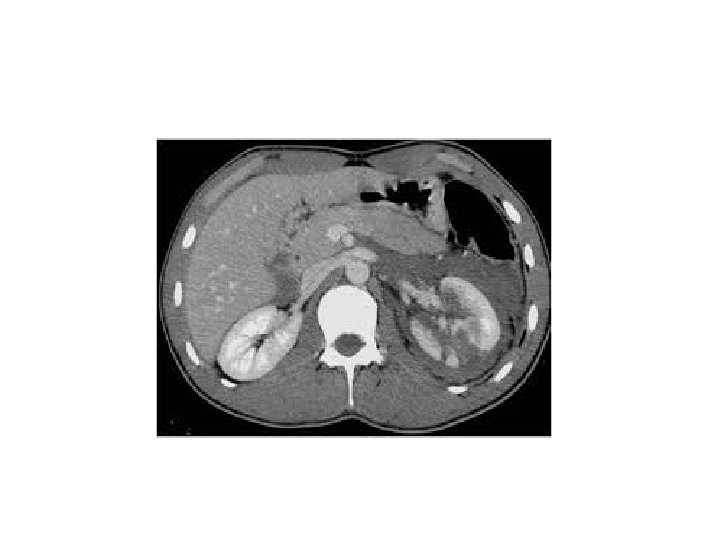

Whom to work up • Penetrating trauma: EVERYONE • Pediatric patients with microscopic hematuria. • Blunt trauma: Image with CT if: • gross hematuria • microhematuria plus shock • microhematuria plus acceleration/deceleration Mee et al. (1989) Hardeman et al (1987

Imaging of trauma patient with hematuria • CT preferred – With contrast – With “delayed” films (mandatory) – Why not get CT cystogram too? • Standard intravenous pyelogram (IVP): Forget it • “One Shot” intraoperative IVP – 2 cc/kg intravenous contrast – Single film at 10 minutes

Bladder: Diagnosis CT Cystography • • • Preferred, especially if already getting other CTs Antegrade filling by “clamping the Foley” is not OK! Must dilute contrast (6: 1 with saline, or to about 2 -4%)

Bladder: Diagnosis CT Cystography Extraperitoneal Intraperitoneal